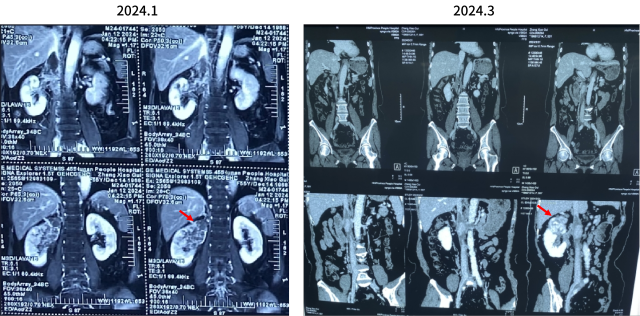

2024.1检查报告

CT检查报告 | 1.左肺动脉主干及分支、右下肺动脉分支多发肺栓塞; 2.下腔静脉、右肾静脉及其属支、左肾静脉及左侧髂总静脉多发血检形成,请结合临床。 3.双肺散在炎症,双侧胸膜增厚; 4.右肾大片状低强化灶,请结合临床。 | 日期 | 2024.1.10 |

CT检查报告 | 1.左肺动脉主干及分支多发肺栓塞较前范围扩大,右上肺后段动脉、右中肺外侧段动脉内肺栓塞,右下肺动脉分支内肺栓塞较前稍吸收减少; 2.右肾静脉及其属支充盈缺损较前相仿,左肾静脉充盈缺损较前范围缩小,下腔静脉、左侧髂总静脉内多发充盈缺损较前范围扩大; 3.双肺散在炎症较前減少,双侧胸膜增厚; 4.左肺上叶尖后段磨玻璃结节,性质待定 建议复查; 5.右肾大片状低强化灶,请结合临床。 | 2024.1.22 |

伏罗尼布+依维莫司新辅助靶向治疗

CT检查报告

1.左肺动脉主干及分支、右下肺动脉分支多发肺栓塞;

2.下腔静脉、右肾静脉及其属支、左肾静脉及左侧髂总静脉多发血检形成,请结合临床。

3.双肺散在炎症,双侧胸膜增厚;

4.右肾大片状低强化灶,请结合临床。

日期:2024.1.10

CT平扫+增强

检查诊断:

1.下腔静脉管腔较前缩小、充盈缺损较前略减少;

2.右肾静脉栓子同前;左肾静脉充盈缺损未见显示;双侧骼静脉充盈欠佳;

3.右肾上极病变同前:恶性肿瘤可能;右肾盂管壁增厚强化:受累?

4.盆腔少量积液;

5.右肝动脉起自肠系膜上动脉;左下肺动脉栓子;

日期:2024.3.3

CT 报告

1.下腔静脉管腔较前缩小、充盈缺损较前减少;

2.右肾静脉栓子较前减少;右侧髂总静脉内少许栓子;

3.右肾上极病变较前缩小,右肾孟管壁受累较前减轻;

4.盆腔少量积液较前减少;

5.左下肺动脉栓子形成,范围较2024-01-22日稍缩小;

6.左肺上叶结节较前稍增大,性质待定;

7.双肺下叶少许条索较前减少。

日期:2024.3.21